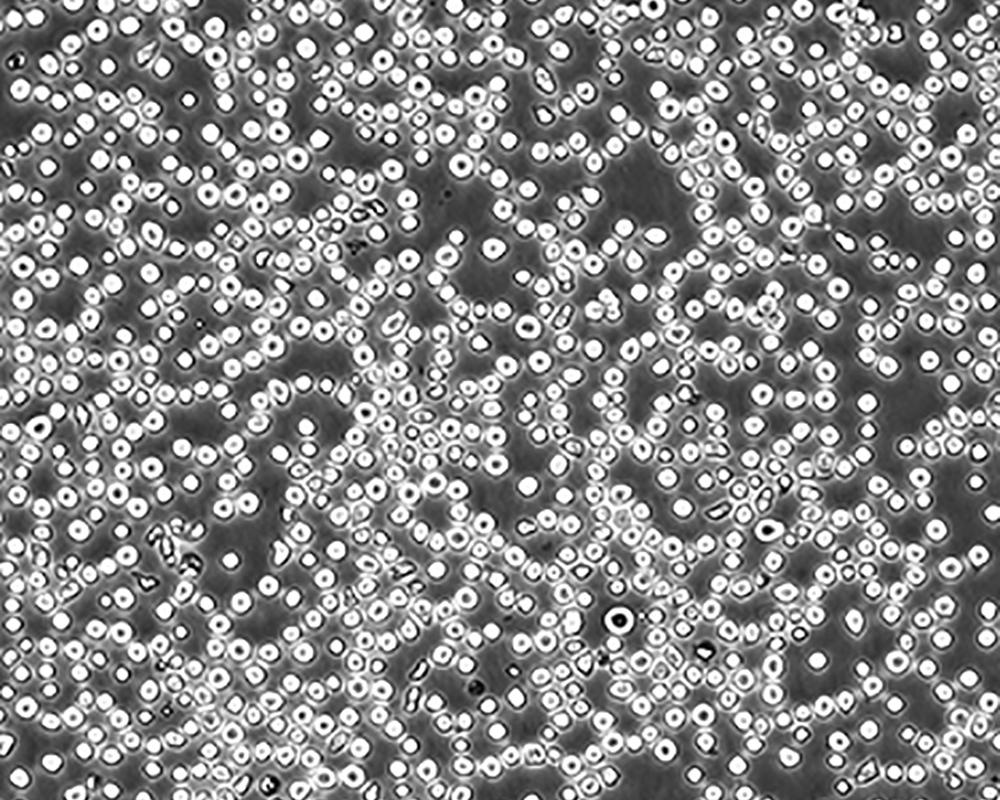

生長特性 suspension

形態(tài)特征 lymphoblast

傳代方法 1:2-1:4

細(xì)胞傳代步驟 如果細(xì)胞密度達(dá)80%-90%,即可進(jìn)行傳代培養(yǎng)。1. 棄去培養(yǎng)上清,用不含鈣、鎂離子的PBS潤洗細(xì)胞1-2次。2. 加2ml消化液(0.25%Trypsin-0.53mM EDTA)于培養(yǎng)瓶中,置于37℃培養(yǎng)箱中消化1-2分鐘,然后在顯微鏡下觀察細(xì)胞消化情況,若細(xì)胞大部分變圓并脫落,迅速拿回操作臺,輕敲幾下培養(yǎng)瓶后加少量培養(yǎng)基終止消化。3. 按6-8ml/瓶補(bǔ)加培養(yǎng)基,輕輕打勻后吸出,在1000RPM條件下離心4分鐘,棄去上清液,補(bǔ)加1-2mL培養(yǎng)液后吹勻。4. 將細(xì)胞懸液按1:2到1:5的比例分到新的含8ml培養(yǎng)基的新皿中或者瓶中